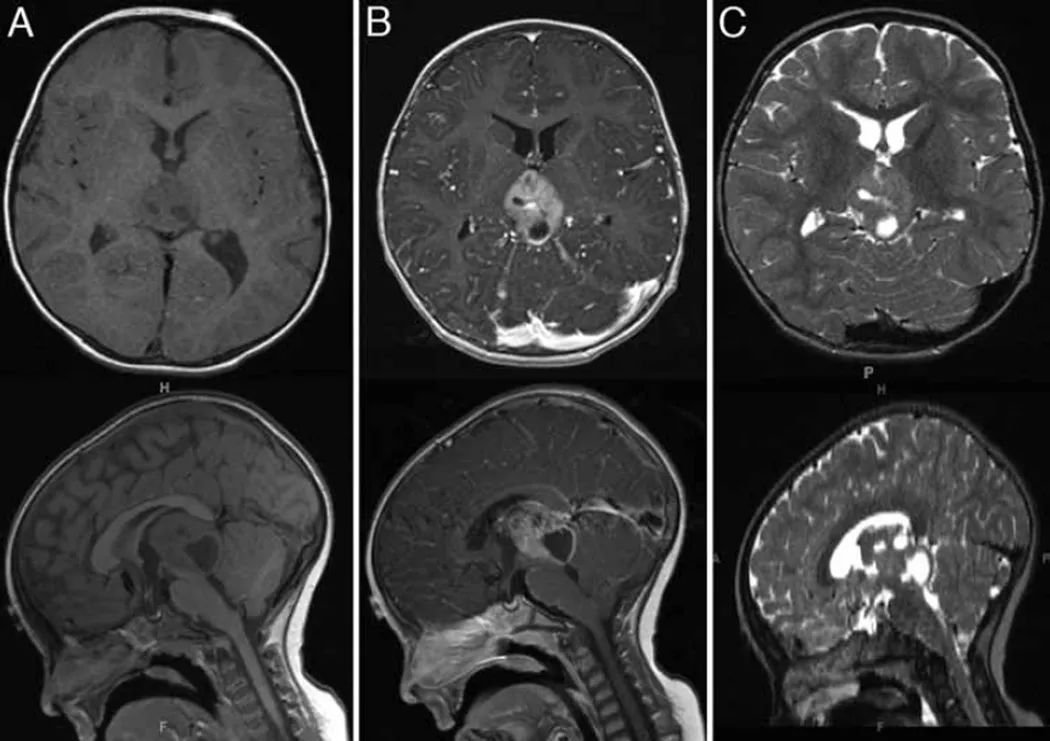

这是一则发布于学术期刊的案例分享,一直很健康的15个月大的男孩因进行性步态障碍伴行为改变1月余入院。初期表现为走路时,他会向左倾斜,撞到物体上,好像他无法避开它们。此外,他出现食欲下降、嗜睡、烦躁和易怒。大约2周后,患儿出现了几天呕吐,并伴有持续5天高烧,还出现腹泻……CT成像显示梗阻性脑积水,进一步检查发现源于松果体区的混合实性和囊性成分肿块。

患儿因梗阻性脑积水接受了第三脑室造瘘术,但术后仍出现间歇性呕吐及眼球运动异常。连续MRI显示松果体区肿瘤在1个月内快速增大并强化,范围延伸至第三脑室后部。鉴于病情进展,行开颅活检及减瘤术,但因切除组织较少未能明确诊断。

随访中肿瘤还在持续生长,孩子开始长期化疗。第二轮化疗后,手术部位出现肿胀,影像学显示肿瘤囊性成分增多伴脑干受压,遂行第三次手术,后续进行质子治疗。

▼第三次减瘤手术前,肿瘤的囊性成分显著增加,导致脑干受压,促使再次手术。